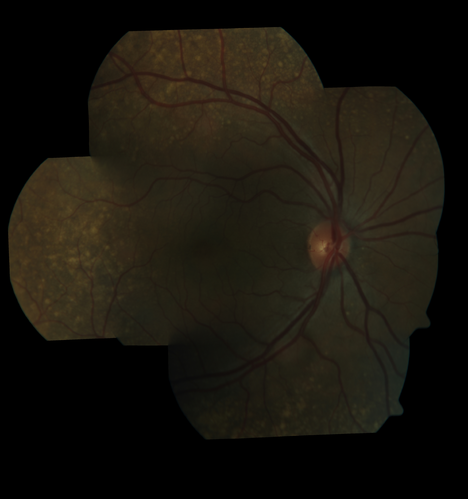

Ocular Lymphoma - non-Hodgkins - B-Cell

Multifocal sub-RPE lesions in the left eye of a patient with history of Non-hodgkins B-cell Lymphoma last active 2 years ago